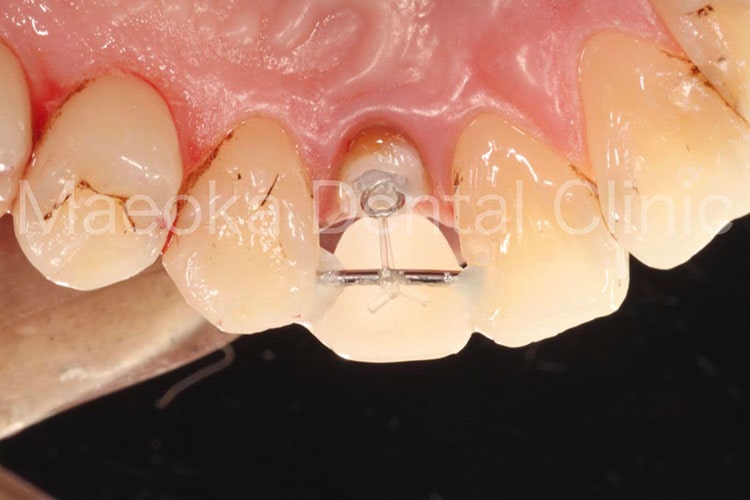

患者さんは39歳男性の方で、「右の前歯の差し歯が取れたので診て欲しい」という主訴で来院されました。お話を伺うと問題の差し歯は前医に通院中、何度も脱落と再着を繰り返していたとのことでした。

差し歯の土台となっている右上2は歯肉上に健全な歯がなく、現在のままでは被せ物を新たに作っても、歯肉にめり込ませるような形でしか入れられない状態でした。

そこで、患者さんと相談した上で右上2に対してExtrusion(歯を引っ張り上げる処置)を行い、歯肉上に健全歯質を確保した上で被せ物をやり直すこととなりました。前歯ということもあり、薄い仮歯を表面に貼り付けることで審美面に配慮しながら治療を進めました。

クラウンレングスニング(歯肉の整形)も行った上で最終的な被せ物をセットして治療を終えています。

現在のところ一度も脱離はなく、良好な経過が得られています。

今後はメインテナンスにて噛み合わせの変化も含めてチェックを行っていきます。

治療中(Extrusion装置)